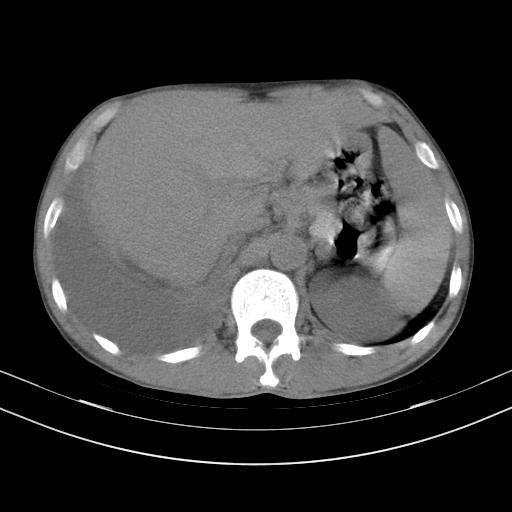

男性,44岁,结核病史多年。现胸闷气短,咳嗽,偶咳血。

右侧胸腔积液

右肺下叶不张

双肺多发结节影最分空洞形成考虑占位不除外结核

双肺陈旧性病变

1、右侧大量胸腔积液伴右肺压缩性膨胀不全,建议抽液治疗后复查 2、两肺继发性tb伴空洞形成。

1)两肺继发性肺结核伴空洞形成,左肺多发性结核球。2)右侧大量胸腔积液伴右肺部分膨胀不全。3)纵隔淋巴结肿大。

吉大一院胸水抽检结果:结核性胸水